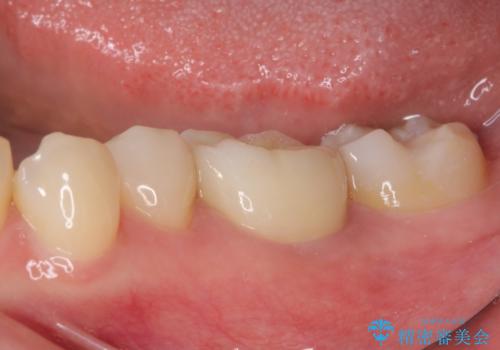

後日状態を確認したところ、残された神経に異常がなかったため、フルジルコニアクラウンにて補綴治療を行いました。